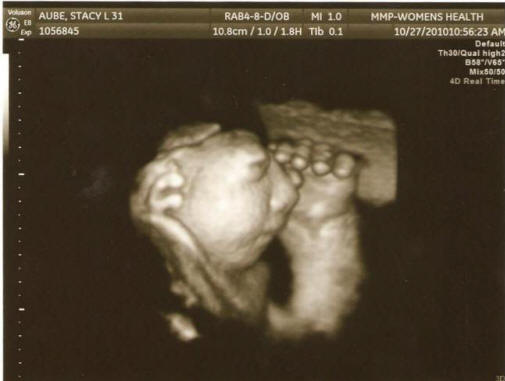

Fotografije iz otvorenih izvora Uključene u istragu stručnjaci su poredili medicinsku dokumentaciju trudnica od 27 područja registrirana u antenatalnim klinikama, proučavaju gdje radili su nego što su bili bolesni, jesu li pili alkohol, drogu ili dimljeni proizvodi, na kojem području su živjeli i od čega izvor je pio vodu. Uostalom, vladini službenici zaključio je da nisu u stanju utvrditi „uslove ili razloge“ ovog fenomena. “Rezultati su bili razočaravajući, ali ne baš neočekivano priznao naučnik Jim Kucik (Jim Kucik), koji je učestvovao u studiji. – Obično takvi urođeni nedostaci uzrokuju kombinacija faktora koju je vrlo teško otkriti. Ne moguće je da je sve ovo samo slučajnost. ” A ovdje je genetska savjetnica Susie Ball vjeruje da u tri okruga U državi Washington postoji neki problem koji bi mu trebalo dati problem pomniju pažnju kako bismo u budućnosti zaštitili žene u rodnom dobu. Oprez, šokantna fotografija.

Fotografija s otvorenih izvora “Ne bih se htjela plašiti ljudi, ali ono što se događa me alarmira “, naglasila je. – Primljeno od informacije o medicinskom osoblju trebaju biti široko objavljene, da žene u rodnoj dobi poduzimaju sve potrebne mjere sprečavaju razvoj ove patologije. Za početak ih savjetujem uzmi folnu kiselinu. ” Naučnici su već pročitali rezultate prethodne studije koje identificiraju potencijalne faktore rizik od razvoja anencefalije: niski prehrambeni folati kiselinama, izloženosti pesticidima i zagađenju pitke vode nitrati.